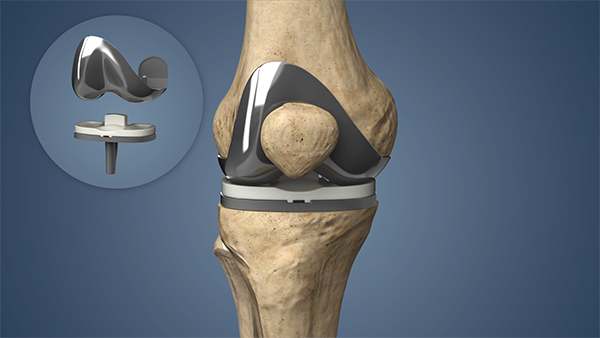

- Definition: Total joint replacement, also known as arthroplasty, involves replacing the entire damaged or arthritic joint with a prosthetic implant. This procedure is typically performed when arthritis affects the entire joint or when other treatments have been ineffective in providing relief.

- Procedure: During a total joint replacement, the orthopedic surgeon removes the damaged bone and cartilage surfaces of the joint and replaces them with prosthetic components made of metal, plastic, or ceramic materials. The artificial joint mimics the natural joint’s shape and function, providing smooth movement and reducing pain.

5. Considerations: Total joint replacement requires a larger incision and more extensive surgical approach compared to partial joint replacement. Recovery may take longer, and rehabilitation is essential to regain strength, flexibility, and joint function.

In summary, the main difference between partial and total joint replacement procedures lies in the extent of joint involvement and the surgical approach. Partial joint replacement targets specific compartments of the joint affected by arthritis, preserving healthy tissues and ligaments. Total joint replacement, on the other hand, replaces the entire joint surface with artificial components, providing comprehensive relief for advanced arthritis affecting the entire joint. Both procedures have their indications and benefits, tailored to the individual patient’s condition and goals for joint function and pain relief.